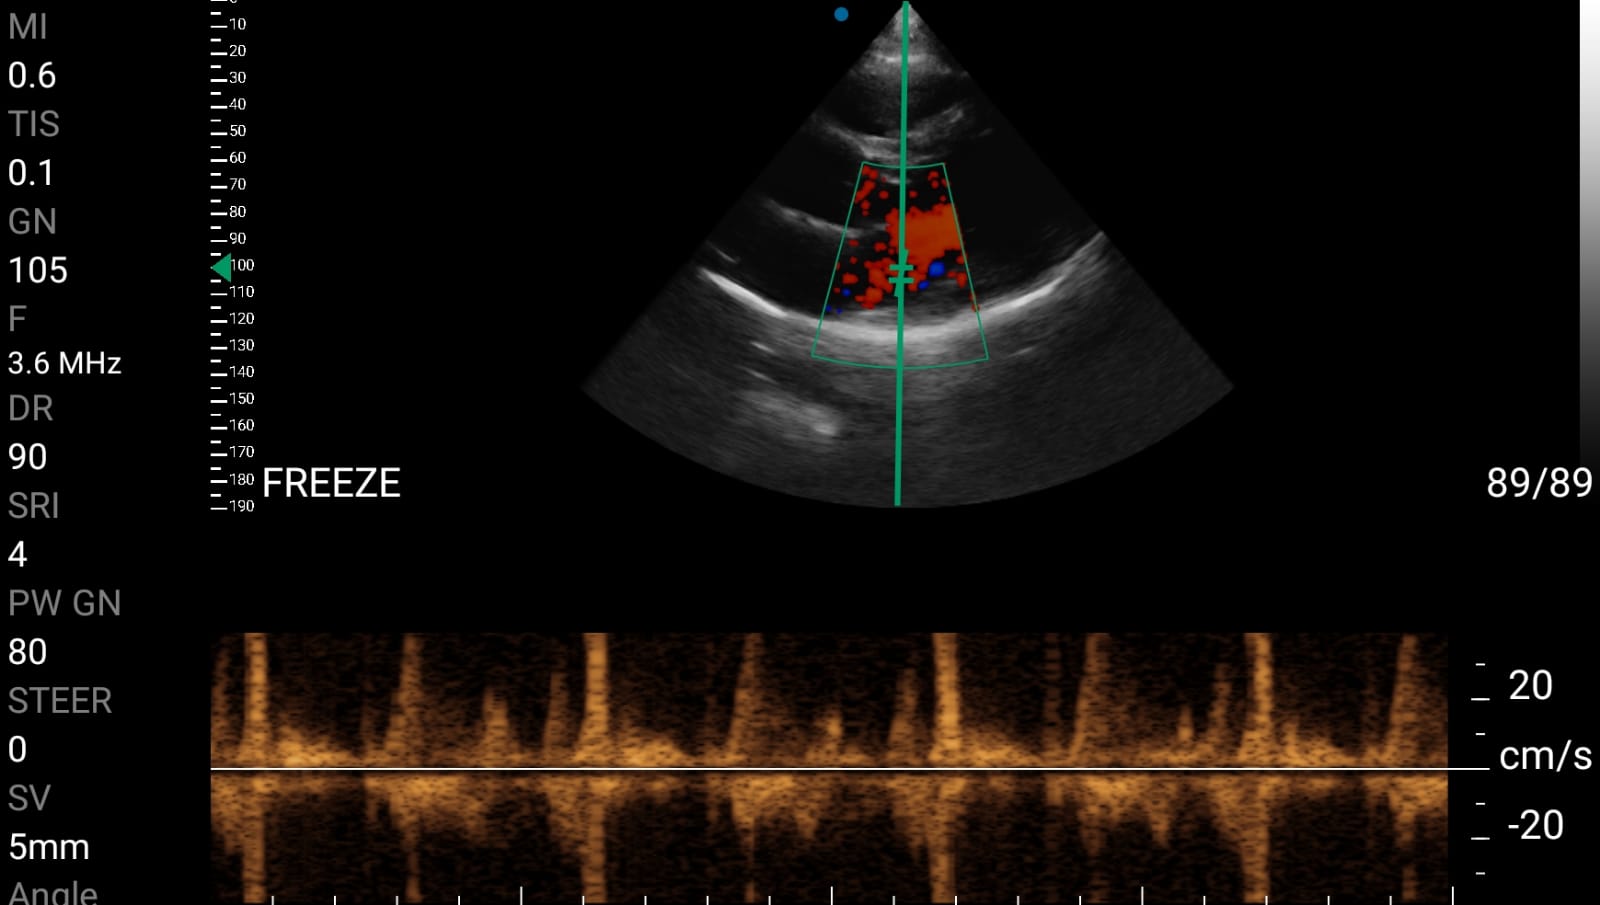

• Doppler καρδιακών βαλβίδων: Βασική εκτίμηση στένωσης/ανεπάρκειας.

• Διαστολική δυσλειτουργία: Εκτίμηση πληρότητας της αριστερής κοιλίας.

Παραδείγματα

Ολες οι παραπάνω απεικονιστικές εξετάσεις έχουν ληφθεί από φορητή συσκευή όπως: Apple Iphone, Tablet, Samsung Mobile Phones και διάφορες άλλες φορητές συσκευές.

Παραδείγματα Video